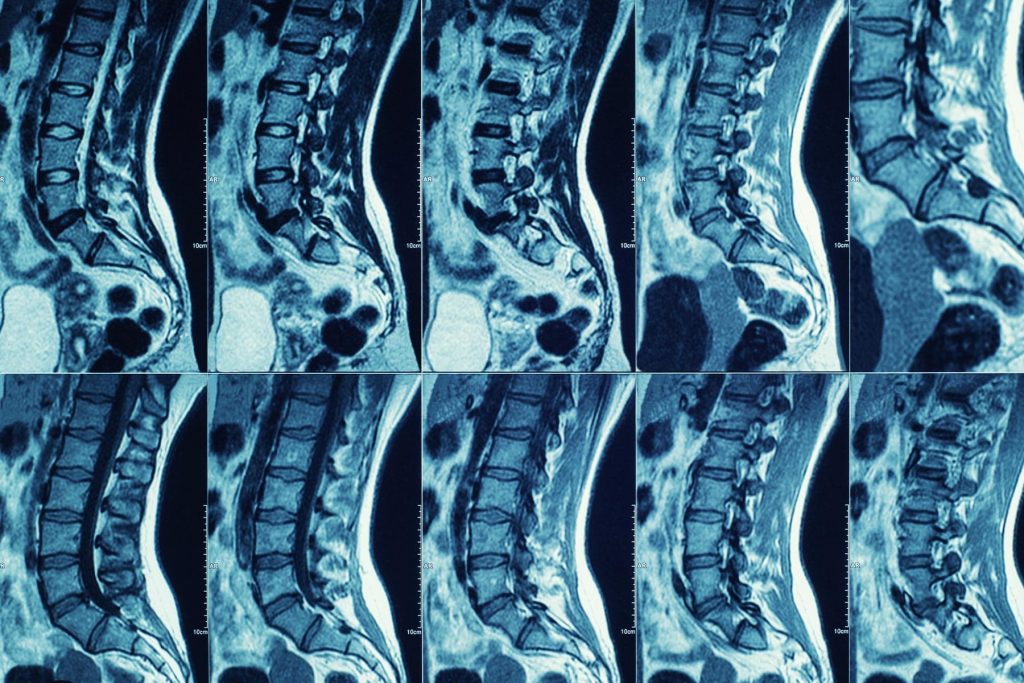

Annually, there are an estimated 17,730 new spinal cord injuries in the U.S. and 250,000 to 500,000 worldwide. The U.S. Senate has designated September as National Spinal Cord Injury Awareness Month.